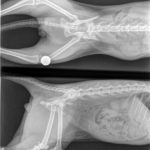

Le han dado un fuerte golpe y le han roto la cadera por dos partes, lo que le ha hecho perder casi por completo la movilidad de la parte trasera del cuerpo.

A pesar del calvario que ha vivido, se ha mostrado siempre muy tranquilo y muy noble. Se ha dejado manipular perfectamente sin quejarse, hasta el momento de hacer las radiografías porque no puede soportar el dolor.